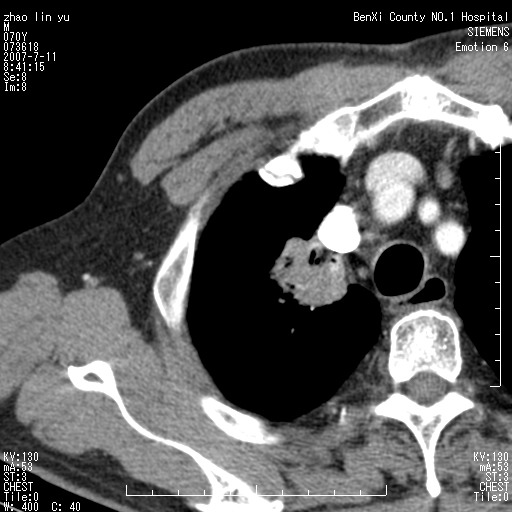

以下是引用王靖旗在2007-7-10 17:12:00的发言:[br] 男、70、咳嗽两个月,半年前换瓣手术,胸片未见异常,于昨天行x片发现右肺上野大片影,行ct扫描,这里是减薄图像,余肺正常。明天晚上会有增强扫描片,到时我会上传。[br][br] 冠状位请大家细看,应该是有意义的,[br][br] 请大家先看平扫发表意见。[br][br]

以下是引用zhangzhongshou在2007-7-10 21:43:00的发言:[br]右肺上叶周围型肺癌,以孤立型细支气管肺泡癌可能性大。